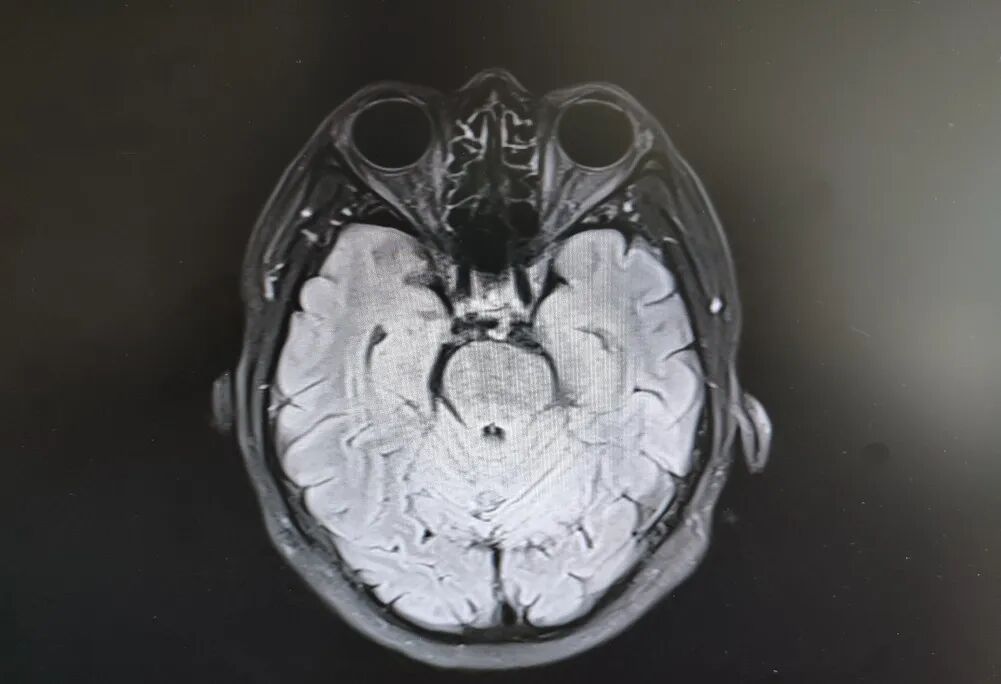

患者头部磁共振影像

就在看似陷入僵局时,关键的血液检查结果出来了——RPR阳性!这个结果像一盏明灯,指明了方向。原来,导致大爷眼病的幕后黑手,竟是由苍白密螺旋体(引起梅毒的病原体)感染引起的神经损害。经过针对性治疗,十几天后,大爷的病情逐渐好转,眼皮能抬起来了,重影消失了,眼球转动也灵活了!